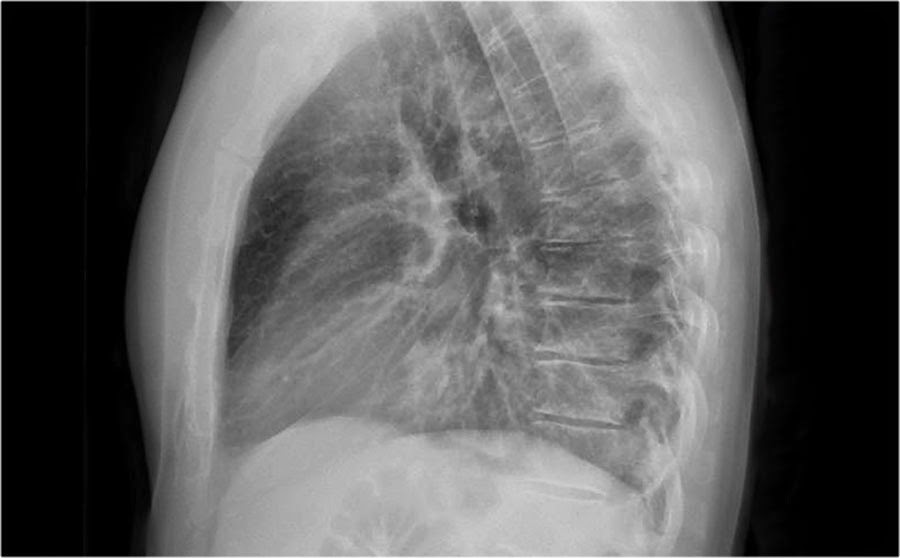

Patient has shortness of breath and purulent sputum. Lateral chest X ray is shown here. What does it show?

1. more black sign pointing fluid, mass, consolidation..the lower vertebral bodies should be more radiolucent